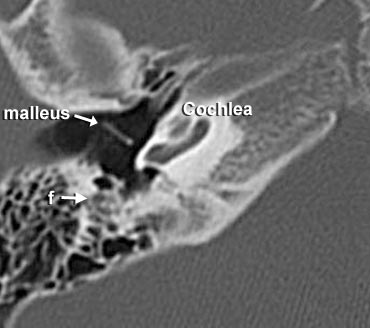

- A = Hang chũm (Antrum)

- f = Dây thần kinh mặt

- long crus = Ngành dài của xương đe

Giải phẫu axial từ dưới lên trên

Ở mức thấp nhất, ta thấy dây thần kinh mặt đi xuống dưới để cuối cùng đến lỗ trâm chũm (stylomastoid foramen) (không hiển thị trong hình này).